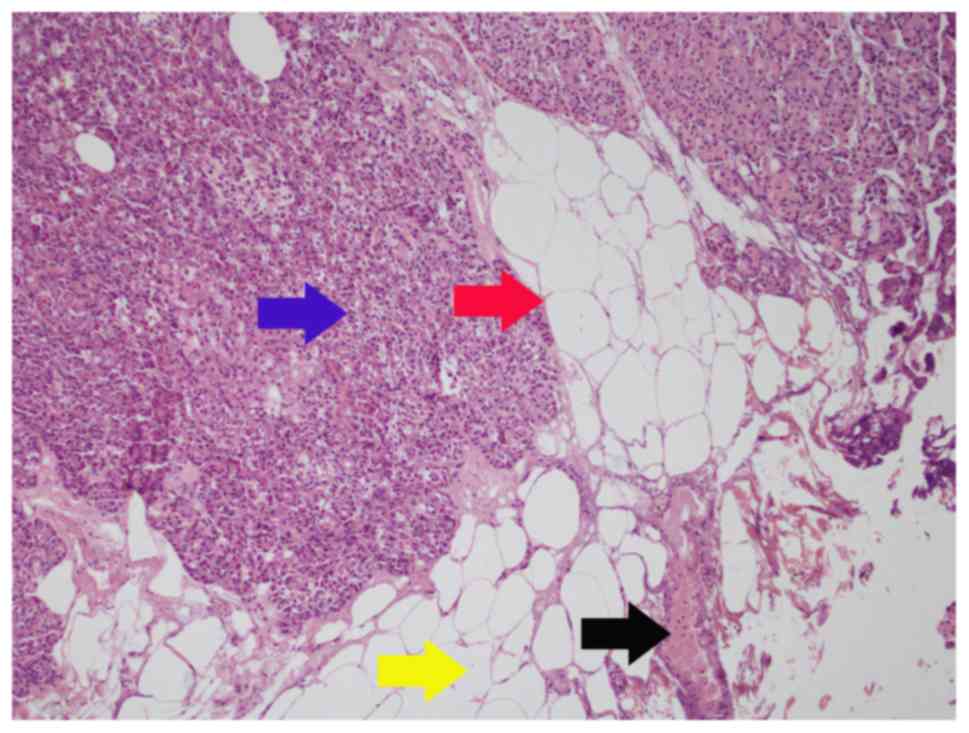

Figure 3.

Sub-classification criteria type C: Tumor nodules distributed in perinephric adipose tissues. Blue arrow, tumor; red arrow, pseudo-capsule; yellow arrow, adipose tissue; black arrow, tumor nodules like an island. Hematoxylin-eosin staining. Magnification, ×200.

Results

The third pathological subtype is a rare type characterized by tumor nodules that are distributed in the perinephric adipose tissues. The tumor nodules are like islands distributed among the perinephric or the renal sinus adipose tissues. After PN, despite the complete removal of adipose tissues covering the kidney surface, it is still difficult to completely remove the tumor nodules that are scattered in the perinephric fat, as they are invisible to the naked eye. Thus, a radical resection should be performed for this subtype. However, since the tumor nodules cannot be detected by imaging before surgery, cT1a RCC is commonly treated by PN. Therefore, close follow-up is recommended with the upstaging of pT3a RCC in this type. Radical surgery should be performed immediately upon the recurrence after surgery.